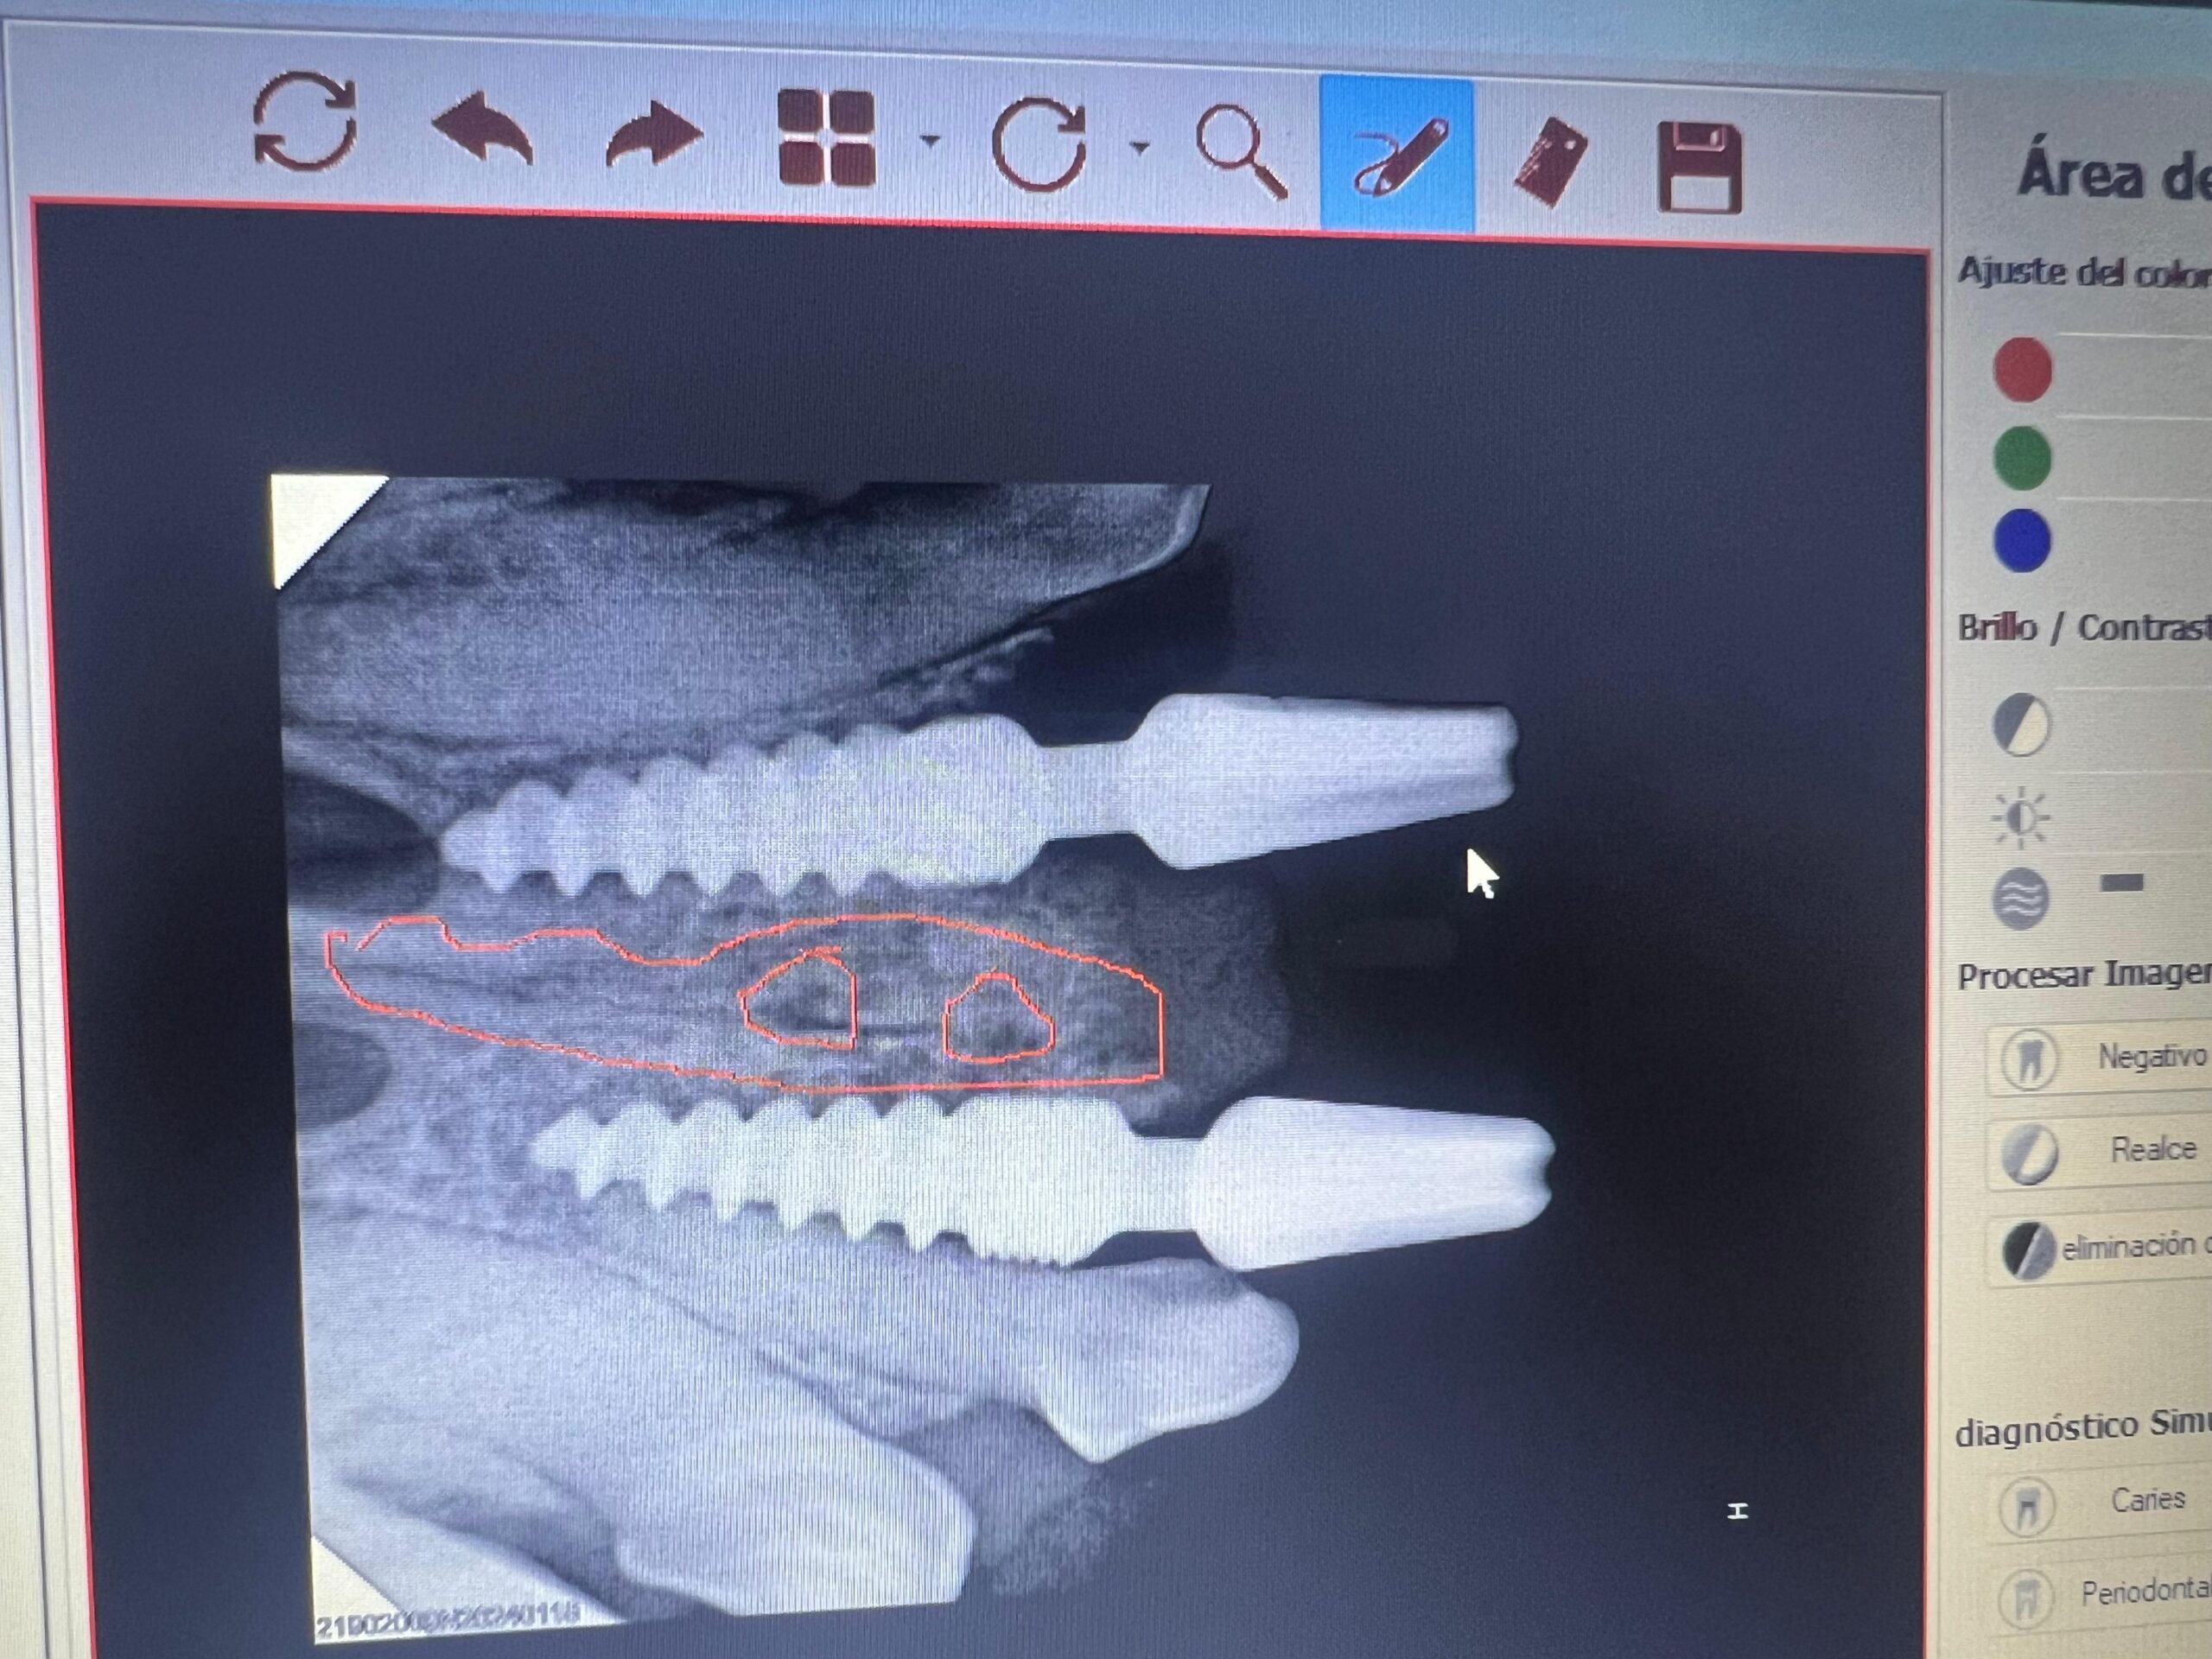

Implantología, planificación y colocación de implantes dentales en el hueso maxilar o mandibular para sustituir piezas dentales perdidas o ausentes. Utilizamos tecnología avanzada para diseñar y rehabilitar sobre ellos la prótesis, garantizando un ajuste y resultado perfecto..

Implantología Dental

Nuestro equipo veterinario especializado combina conocimiento clinico, ingeniería digital y bioseguridad avanzada para ofrecer una experiencia integral. Cada procedimiento se realiza bajo los mas altos estándares de calidad, priorizando el confort, la seguridad y la comodidad de tu compañer@.